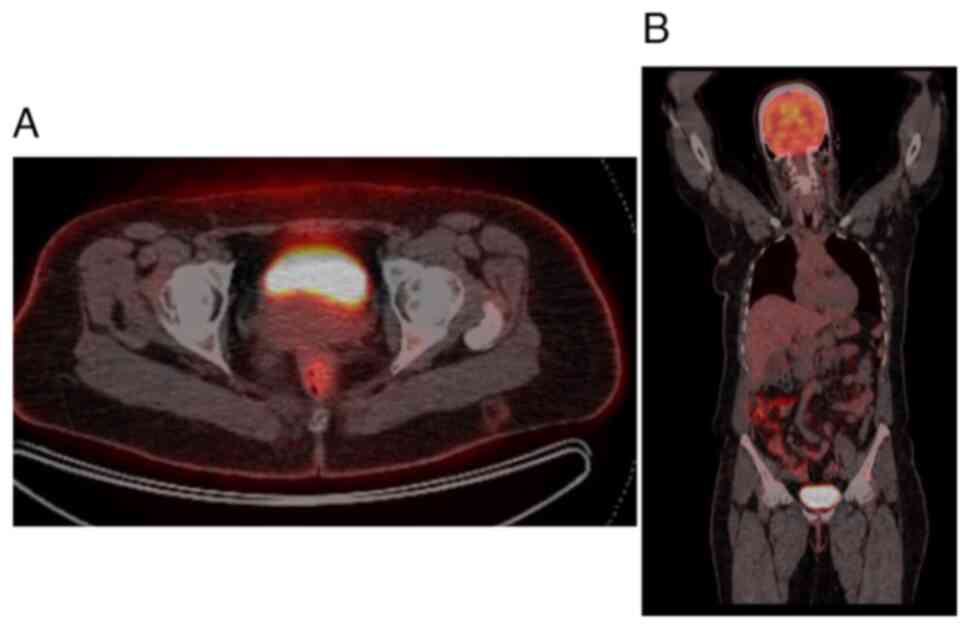

Initial diagnostic workup included an abdominal ultrasound (U/S), which was followed by a contrast-enhanced computed tomography (CT) scan as the previous surgery had been based on the U/S alone. The CT scan was performed to provide a more detailed assessment of the bladder wall and surrounding structures, which revealed irregular, thickened bladder walls (8 mm), but no gross mass lesion due to the previous TURBT procedure (Fig. 2). Given the history of adenocarcinoma and to assess potential metastasis, a fluorodeoxyglucose positron emission tomography (FDG-PET) was recommended by the multidisciplinary team. The FDG-PET was crucial for detecting any hypermetabolic nodular lesions suggestive of metastatic spread; however, the results revealed no abnormal focal hypermetabolic nodular lesions in the urinary bladder wall or elsewhere in the body (Fig. 3). Based on the PET scan findings and the initial TURBT biopsy, which revealed a T2-stage adenocarcinoma, a radical cystectomy was advised for definitive management.

Figure 3

(A) PET-CT axial sections of the pelvis illustrating that radioactive substances are excreted in the urinary bladder with no abnormal uptake in the pelvis. (B) Whole-body PET-CT coronal section shows normal uptake in the brain and intestine, excretion in the urinary bladder, and no metastasis.